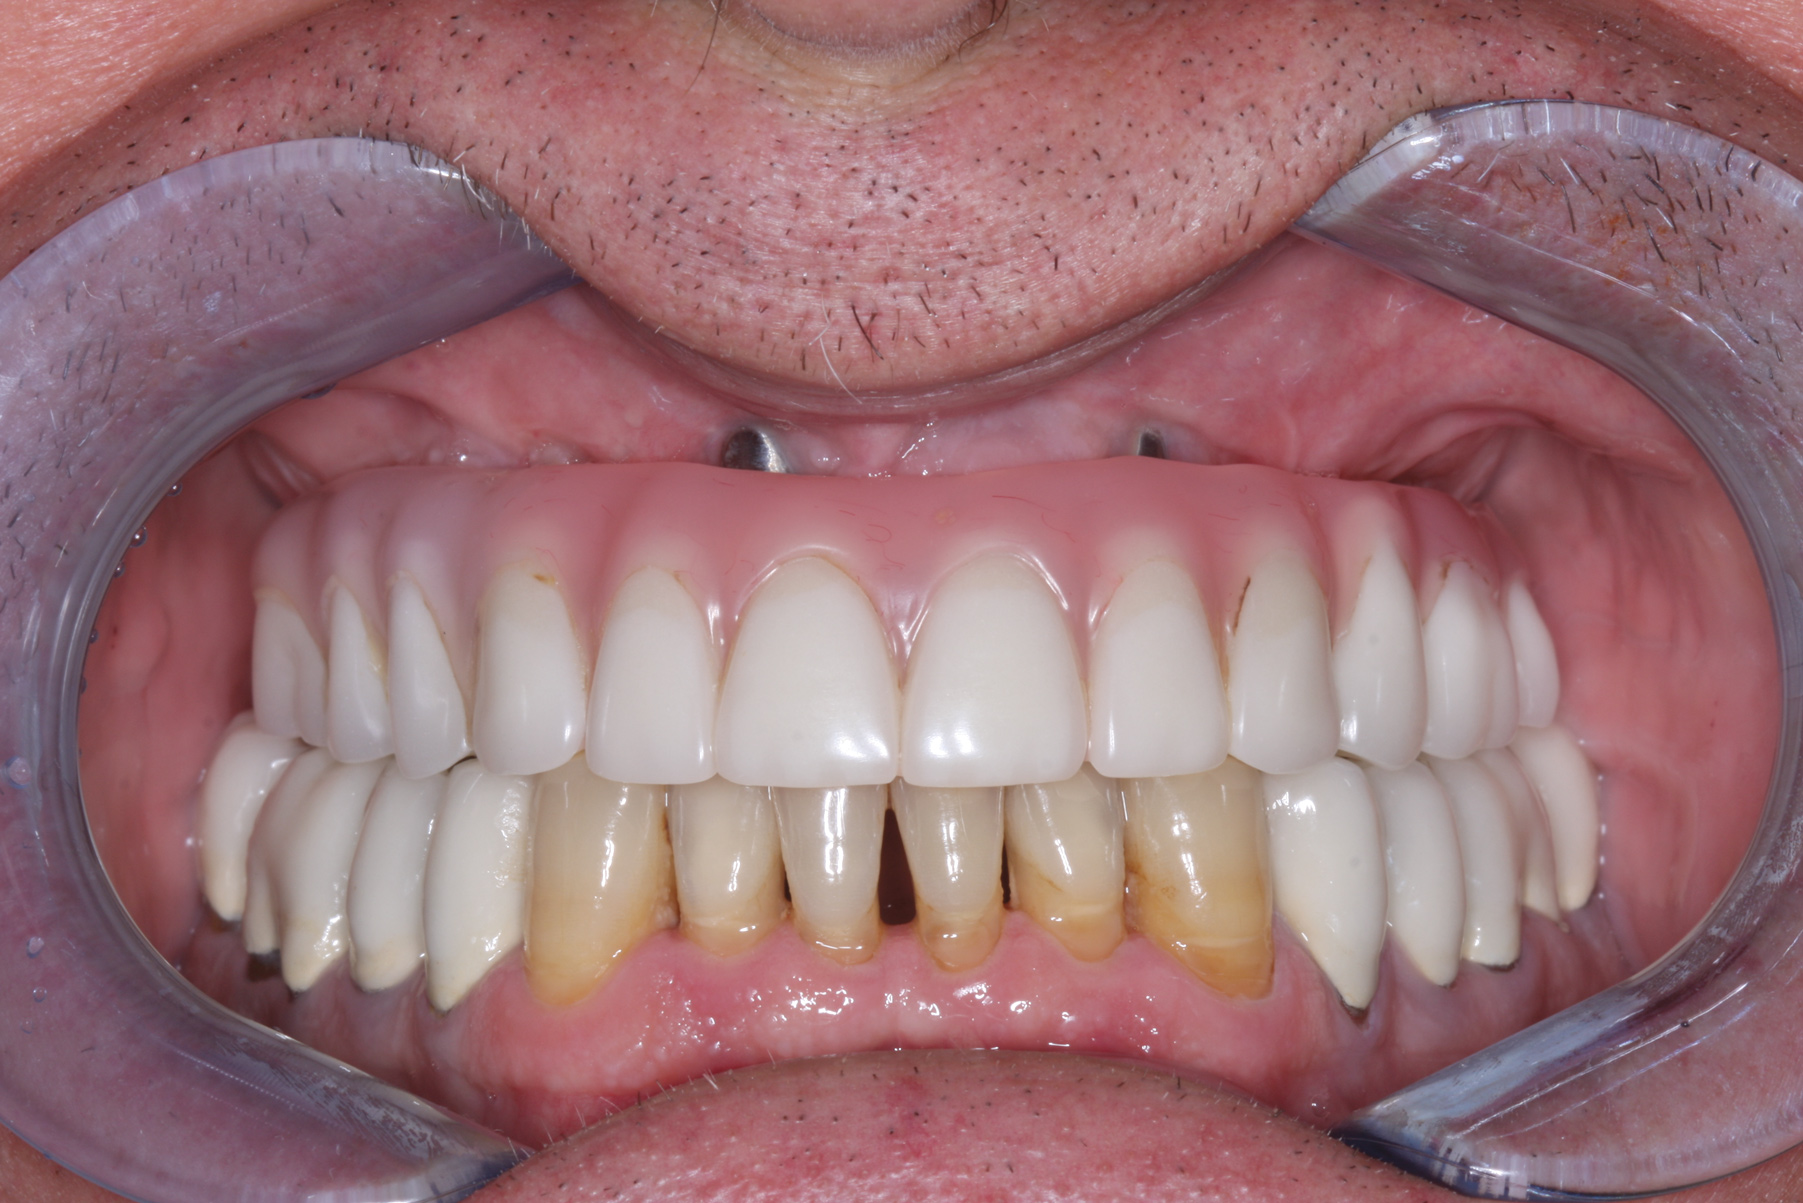

A 61-year-old man residing in Ohio was referred to the author's New Jersey practice for diagnosis and treatment of a failing maxillary hybrid prosthesis (Figure 1). The patient's maxillary teeth had been extracted in June 2011, when five implants were placed. Restoration of the maxillary arch was completed in April 2012. Aside from a sensitivity to aspirin and taking 20 mg of atorvastatin per day, the patient's medical history was negative.

Fig 1. Preoperative retracted facial view of a 61-year-old man who presented with a failing maxillary hybrid prosthesis.

Figure 1

Fig 11. Preoperative close-up retracted facial view revealed extensive and unesthetic mandibular tooth wear.

Figure 11